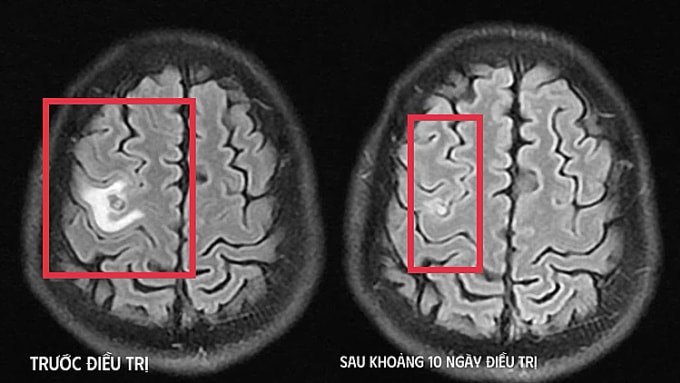

Bác sĩ chụp cộng hưởng từ (MRI) sọ não, phát hiện tổn thương dạng nang nhỏ tại thùy trán trái, xung quanh có phù não nhẹ. Hình ảnh này hướng nhiều đến tổn thương do ký sinh trùng hơn là u não nguyên phát. Người bệnh tiếp tục được chỉ định xét nghiệm, kết quả dương tính sán dây chó. Bác sĩ chẩn đoán tổn thương não do ký sinh trùng, điều trị nội khoa theo phác đồ, kết hợp kiểm soát triệu chứng và theo dõi sát diễn biến thần kinh. Sau khoảng 10 ngày, tình trạng bệnh nhân cải thiện rõ rệt.